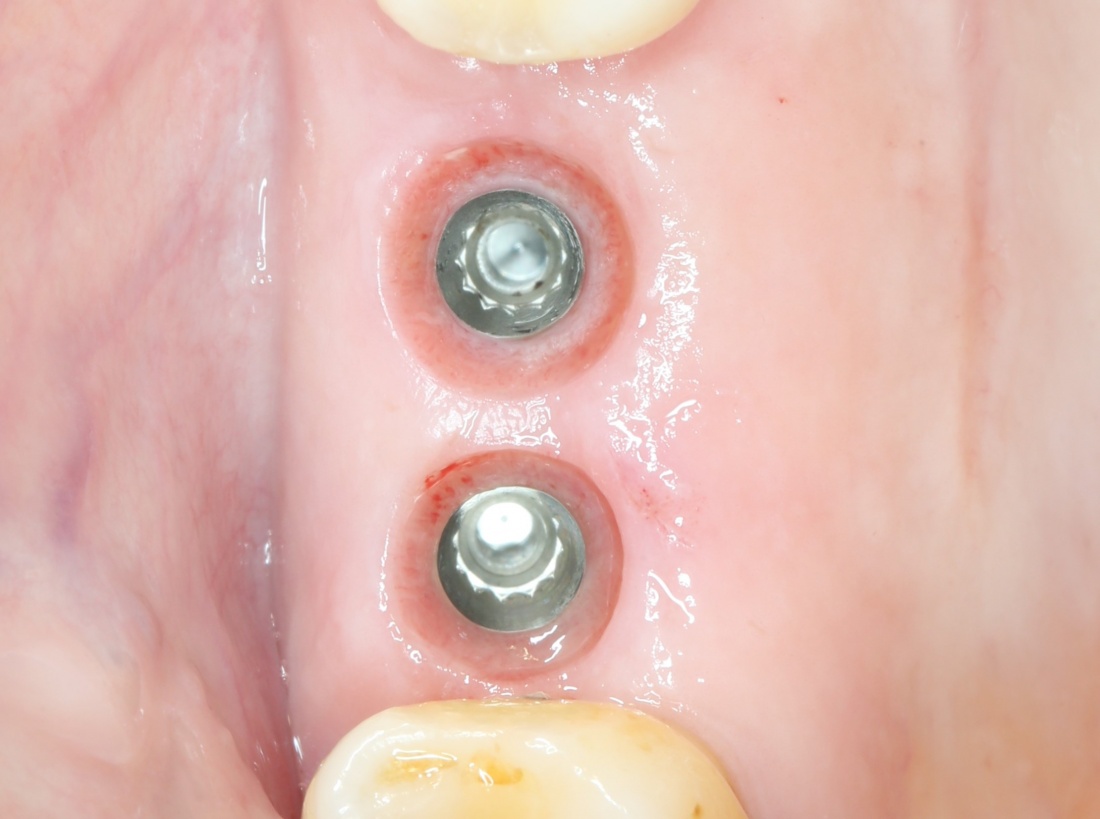

Через три месяца мы сняли коронки с имплантатов, чтобы оценить качество формирования десневого контура:

С этого момента можно перестать переживать — десневой контур сформировался правильно, мы получили достаточный объём и качество окружающей платформу имплантата десны. Можно приступать к изготовлению постоянной протетики. Подрядчиком стала зуботехническая лаборатория French Creative, одна из топовых лабораторий Москвы.